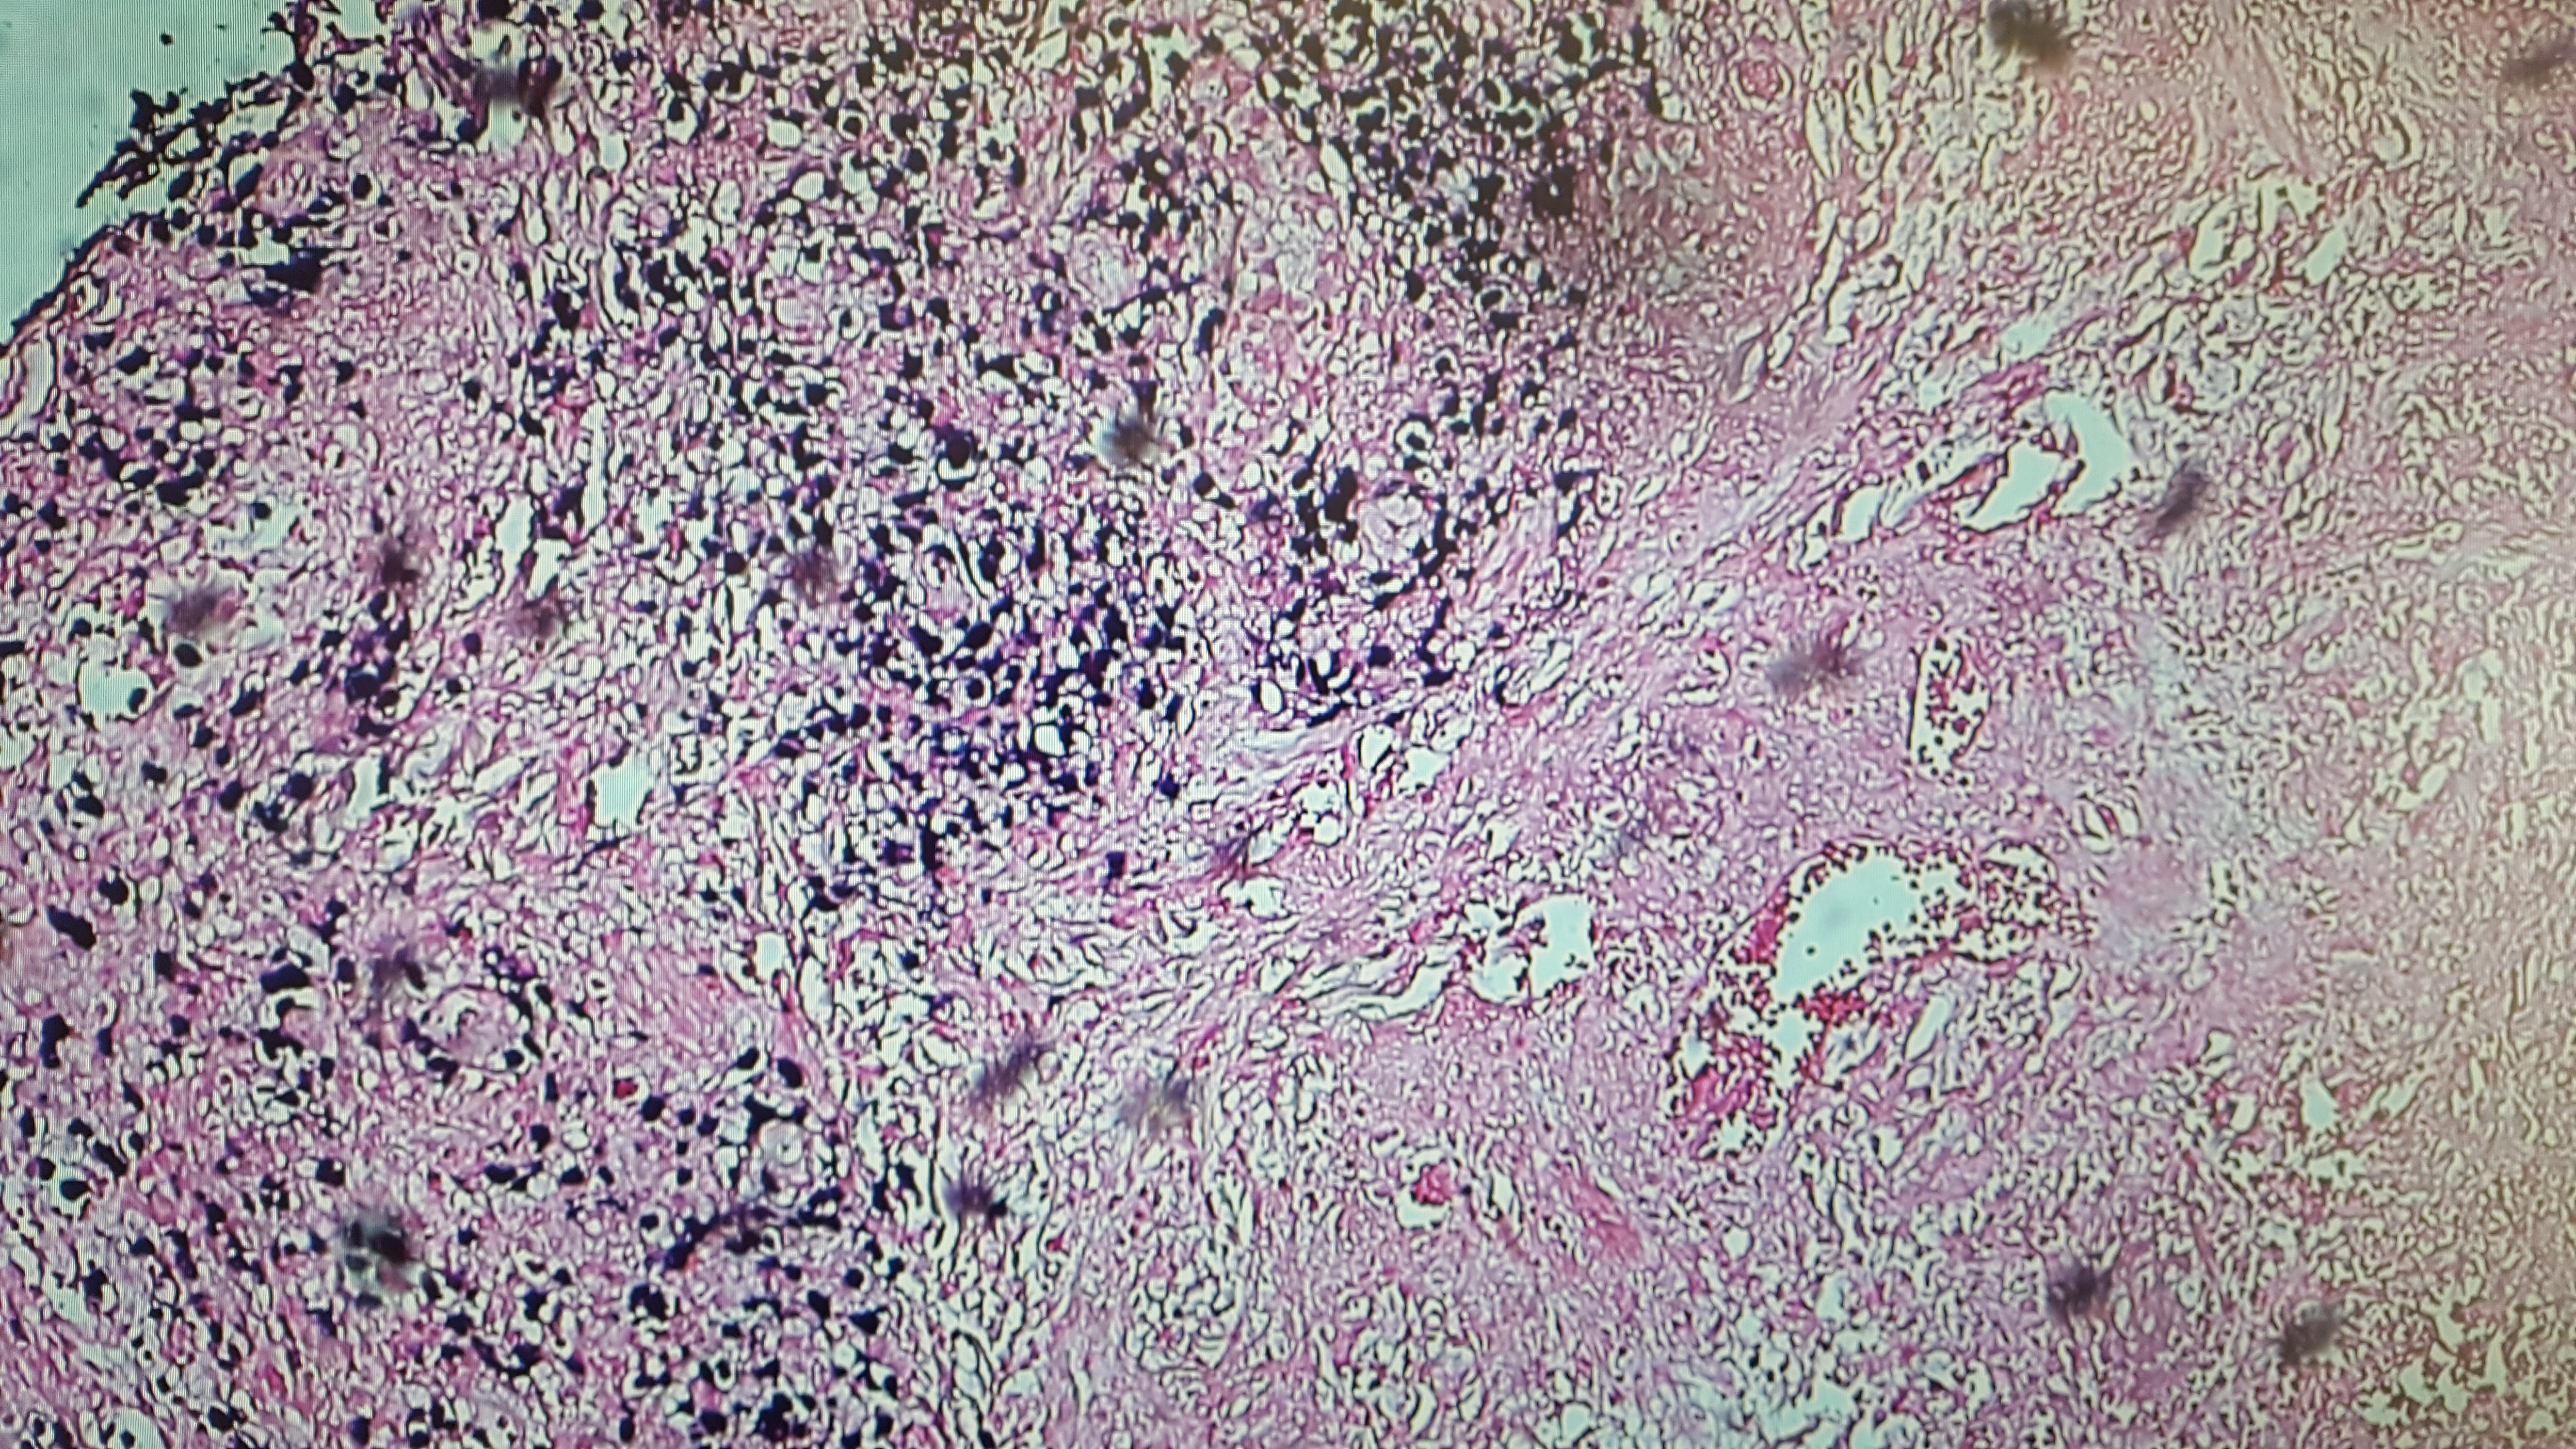

The final pathology report of the skin biopsy showed positive immunohistochemical staining for CD2/3-positive T cells with predominantly infiltrating CD4+ cells. CD20+ cells predominated around blood vessels, with evidence of Epstein-Barr virus (EBV)–positive cells infiltrating the tissue and blood vessels (Figures 3 and 4). Immunohistochemical staining was negative for CD56, ruling out the initial diagnosis of NK/T-cell lymphoma.

Figure 4. Epstein-Barr encoding region (EBER) in situ hybridization demonstrating positivity for EBV.